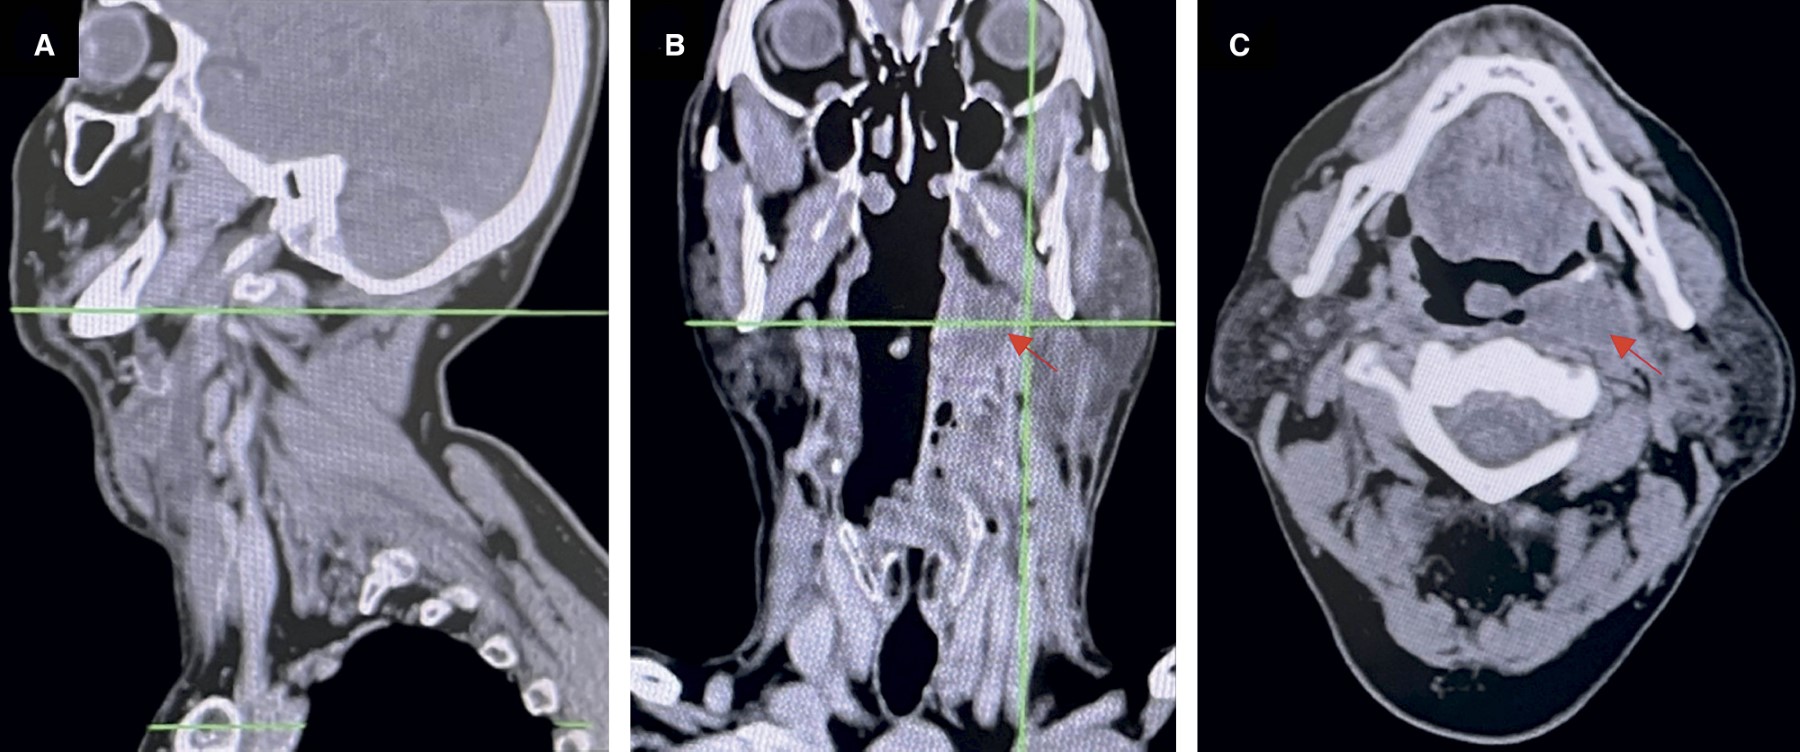

En la exploración física se evidenció aumento de volumen cervical doloroso y masa fluctuante periamigdalina izquierda, sin trismus. La tomografía computarizada con contraste de cuello mostró colección periamigdalina izquierda con extensión a los espacios retrofaríngeo y parafaríngeo, márgenes mal definidos y desviación de la vía aérea hacia la derecha, sin obstrucción completa (Figura 1).

Figura 1